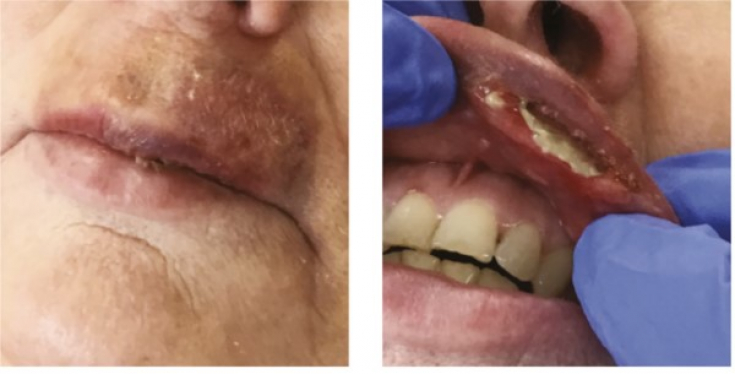

Під час ін'єкції на верхній губі з'явилося щось, що нагадує гематому (Мал.1).

Мал. 1: 1 день після корекції філером – гематома на верхній губі.

Через п'ять днів після початкового лікування шкірним філером пацієнтка вирішила звернутися за додатковою допомогою до Lynn Lowery. Пацієнтка дозволила фахівцеві оглянути губу, незважаючи на сильний біль (Мал. .2).

Рис.2: 5 днів після корекції губ філерамі. >